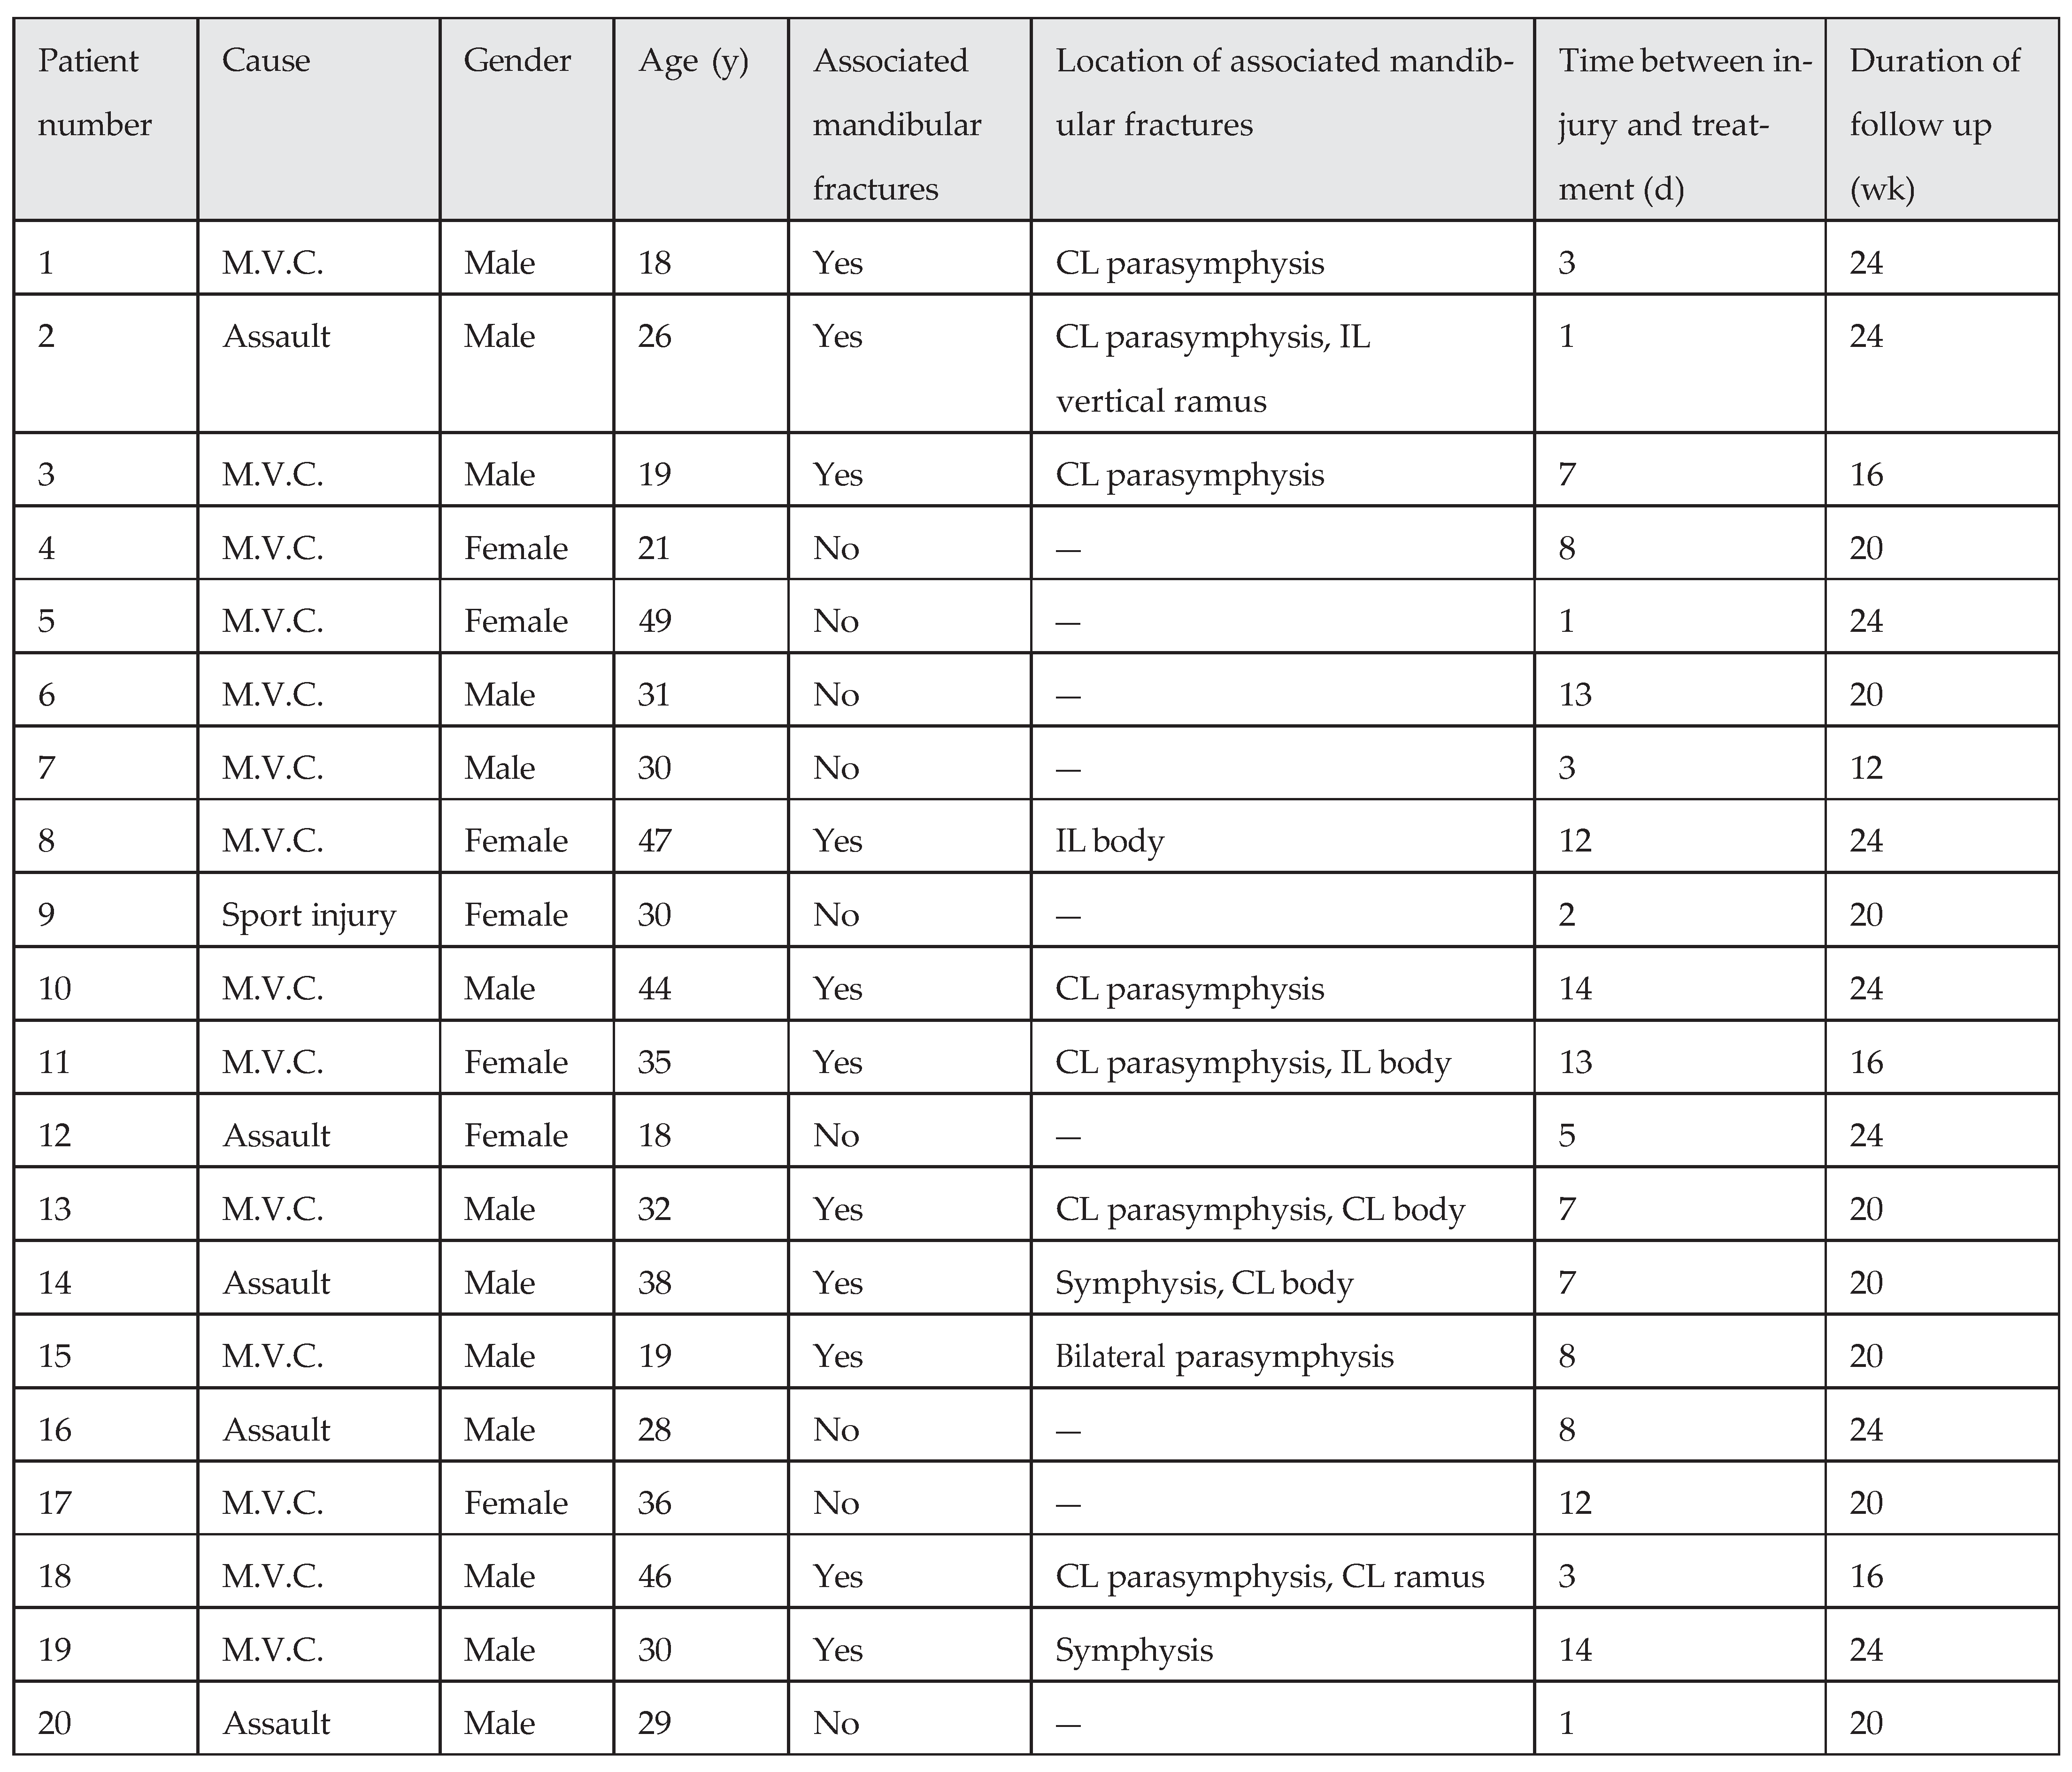

In this study, the most common cause of mandibular angle fractures was motor vehicle crash (

n ¼ 27/40 [67.5%]), followed by assault (

n ¼ 11/40 [27.5%]), and then sports injuries (

n ¼ 2/40 [5%];

Table 1 and

Table 2). Twelve patients were women and 28 patients were men, with ages ranging from 18 to 51 years (mean ¼ 29.75 10.62). In both treatment groups (with or without MMF), the most associated fracture was parasymphysis fracture in the contralateral side (

n ¼ 18/40 [45%]). The interval of time between injury and surgical operation ranged from less than 24 hours to 14 days (mean ¼ 7.20 4.73). All patients were dentulous, so we could place Erich arch bars for MMF or elastic therapy.

Based on statistical evaluation between the two treatment groups, we found that these groups were similar in demo- graphics. Age, gender, cause, associated mandibular fractures, location of associated mandibular fractures, time between injury and treatment, and duration of follow-up were compared. The results revealed a p value of 0.255, 0.496, 0.757, 0.524, 0.624, 0.924, and 0.711, respectively, so differences are not statistically significance (p > 0.05).

First Treatment Group (without MMF) Results

Seven patients were woman and 13 patients were men, with ages ranging from 18 to 49 years (mean 31.30 9.81;

Table 1). Nine patients (45%) had isolated mandibular angle fractures and 11 patients (55%) had associated fractures. Four patients (20%) had a tooth in the mandibular angle fracture line. The mean time between injury and surgical operation and mean follow-up period were 7.10 4.63 days and 20.60 3.50 weeks, respectively.